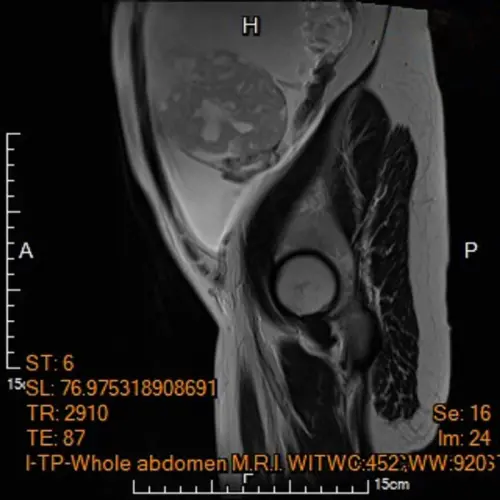

▲孕婦電腦斷層呈現腹水與卵巢腫瘤(圖/馬偕紀念醫院) 陳楨瑞指出,「幼年型顆粒細胞瘤」是一種低度惡性的卵巢腫瘤,主要來自卵巢結締組織,常合併不名原因的多量腹水。傳統卵巢癌在治療上多採取「根除性減積手術」,包括切除子宮、雙側卵巢、輸卵管、淋巴腺與腹腔內轉移之腫瘤,並須搭配術前或術後化學治療,且有相當高的復發與死亡風險。不過李小姐因為合併懷孕中,處理上更為棘手。多方考量下,小心切除腫瘤並讓懷孕延續為治療的最高目標!術後在高危險妊娠科王亮凱接續產檢下,在妊娠38週,自然產下2808公克的健康女寶寶,產後門診追蹤無腫瘤復發跡象,寶寶也十分健康。

一名懷孕5個月的孕婦,在例行性產檢意外發現卵巢有惡性腫瘤,馬偕紀念醫院高危險妊娠科資深主治醫師王亮凱表示,李小姐腹中胎兒發育情況一切正常,但超音波檢查意外發現孕婦腹腔內積滿大量腹水,及左側下腹部有一個15公分大小、邊界模糊、結構複雜的卵巢腫瘤,孕婦反映有明顯的進食與呼吸困難疑似腸胃道問題,為求謹慎,針對腹水檢體進行細胞檢驗,雖未能於腹水內發現癌細胞,腹部核磁共振影像顯示腫瘤疑似來自左側卵巢,且惡性風險極高,高度懷疑是懷孕中合併卵巢癌。